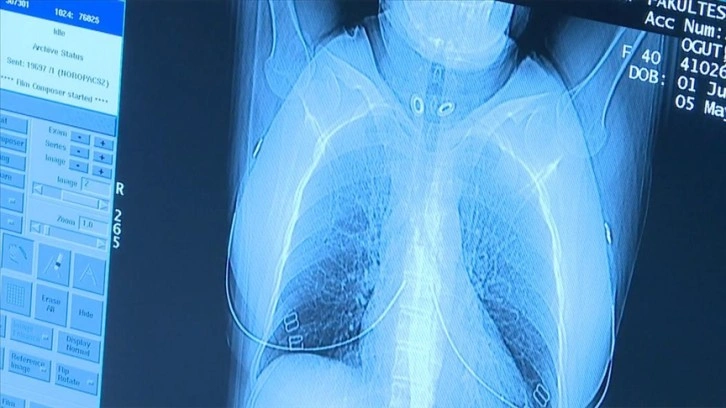

"Düşük doz akciğer tomografisi" ile akciğer kanserinde erken teşhis mümkün

Türk Radyoloji Derneği Yönetim Kurulu Üyesi Prof. Dr. Nermin Tunçbilek, akciğer kanserinde erken teşhisin yüzde 77 oranında hayat kurtarıcı olduğunu belirterek, "50 yaş üzeri ve 20 yıl ve daha uzun süreli sigara içen kişilerde yıllık düşük doz akciğer tomografisi çekilmesi önerilmektedir." dedi.

"Akciğer kanserinde erken tanı ve doğru evreleme ile radyolojik görüntüleme yöntemleri hasta yönetiminde önemli rol oynamaktadır. Akciğer kanserinde erken teşhis yüzde 77 oranında hayat kurtarmaktadır. 50 yaş üzeri ve 20 yıl ve daha uzun süreli sigara içen kişilerde yıllık düşük doz akciğer tomografisi çekilmesi önerilmektedir. Bu sayede, erken dönemde kanser tespiti yapılabilmekte ve tedavisi planlanabilmektedir. Ancak öncelikle kişinin yüksek risk grubunda olup olmadığı hekimi tarafından belirlenmeli ve gerek duyulduğu takdirde tarama yapılmalıdır.

İleri evre akciğer kanserinde tam tedavi oranı büyük oranda mümkün değilken, erken dönemde teşhis ve tedaviyle başarılı sonuçlar alınabilmektedir. Bu nedenle, risk grubundaki kişiler için belirlenen sürelerde düşük doz akciğer tomografisi hayati önem taşımaktadır."